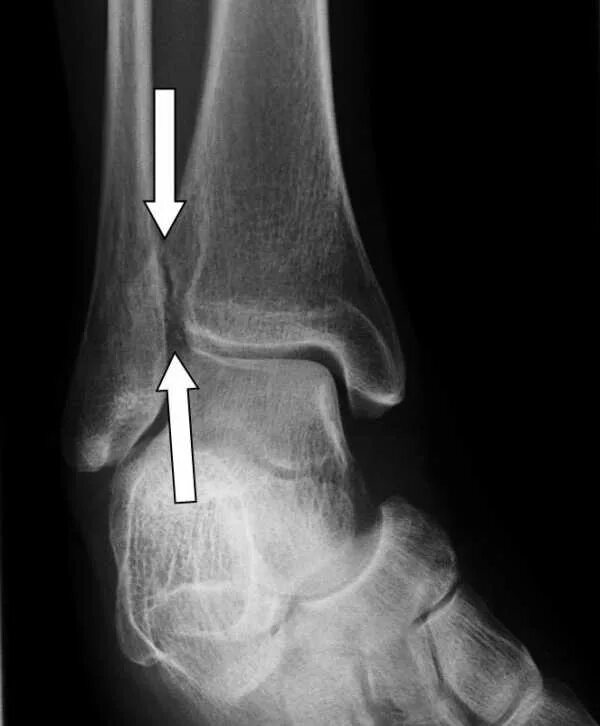

Наружная лодыжка голени